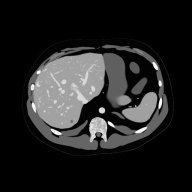

A medical imaging scientist focused on simulating x-ray imaging systems, generating synthetic 3D datasets, and developing AI frameworks for accurate, reliable, and consistent clinical imaging.

- Semiconductor detectors and photon-counting CT modeling

- Synthetic CT datasets of digital humans

- AI for image harmonization